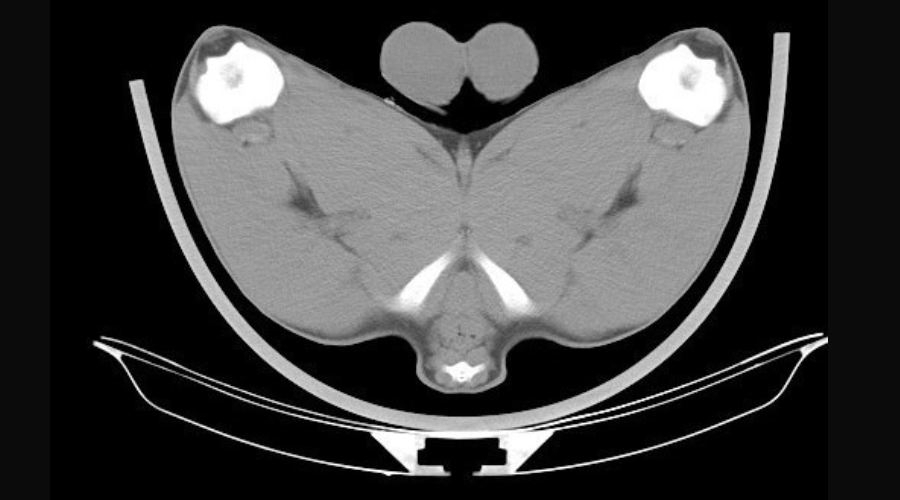

“The CT scanning machine mimics a carcase grader used in abattoirs, measuring the diameter of certain muscles at fixed points around the carcase, calculating muscle dimensions, muscle volume, bone density, internal fat, spine length and pelvic dimensions.

“An x-ray tube moves slowly around the animal, taking cross sectional images of the entire body. These images allow specific anatomical locations and measurements to be recorded as key performance traits, which can aid breeders’ decision-making process when selecting sheep, particularly rams.